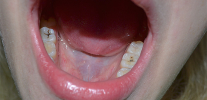

La foto mostra un "nervo" dentale estratto da una camera di polpa: